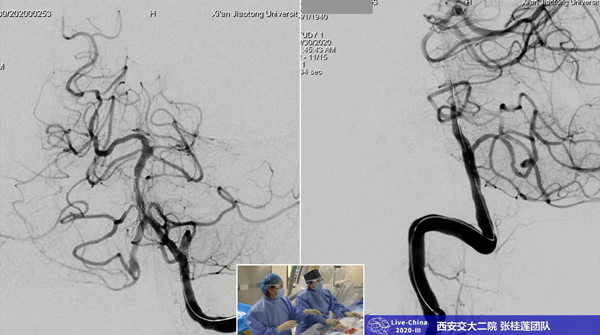

10月30日,由中国卒中学会和中国卒中学会神经介入分会共同举办的“2020中国神经介入互联网直播大会(第三季)》--- Live-China 2020-Ⅲ”神经介入手术演示全国直播活动在线上举行。秉承合作、创新、交流的宗旨,为医务工作者提供国内外神经介入领域最新资讯、指南,聚焦难点深度评论,引领学术前沿。此次直播大会,我院神经内科作为陕西唯一受邀参加单位,与天坛医院、齐鲁医院、河南省人民医院等国内知名的8大神经介入中心演示22台手术,在线观看人员点击量超过15万+。

此次手术演示直播,我院神经内科选择的手术是神经介入难度大、风险高的基底动脉狭窄支架成形术,而且患者系79岁高龄,合并高血压、糖尿病等多种并发症,更增加了手术的风险和难度。术前经过全科讨论,充分准备,对患者病情进行详细评估,尤其是做了我科在国内率先开展的椎基底动脉颅内段平行扫描的BPAS-MRl检查。张主任提前与麻醉科吕建瑞主任充分沟通,在影像科、麻醉科的支持下,由麻醉科赵红霞医师实施全麻,由张桂莲教授主刀,张茹副教授做学术导播全程讲解,展淑琴教授作为一助,张磊医生做二助,护士张倩和蒋鹏鹏辅助手术,范松华博士进行病例汇报。

术中北京天坛医院神经介入科莫大鹏教授、中国医科大学第四附属医院神内高连波教授通过远程直播平台实时点评,对此次直播的手术难度、技术细节等进行点评、交流。历经一个多小时,手术顺利完成,圆满取得预期效果。此次直播利用我院新引进的西门子双C臂血管造影机,充分展示了新型血管造影机在神经介入方面的优势,展示了我院神经内科规范、先进的介入治疗方式和技巧。